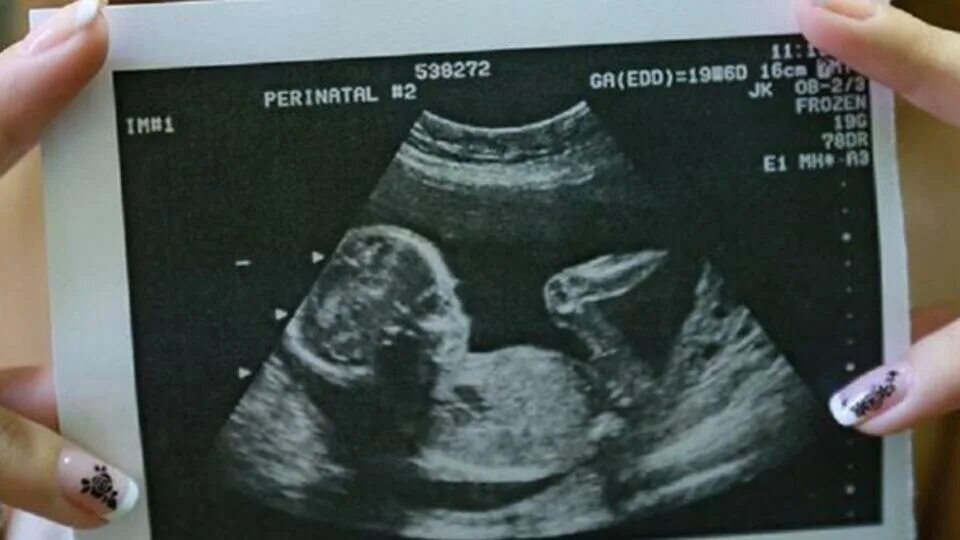

Может ли ошибки узи